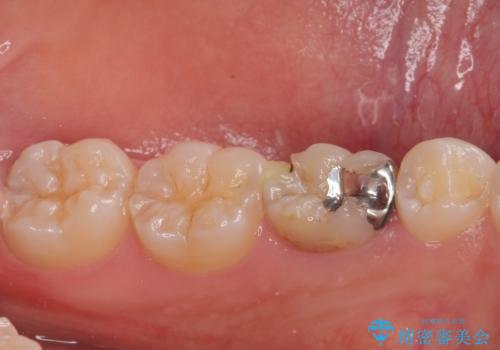

- 左下の乳歯に虫歯ができたので銀歯も外してやり替えたいとのことで来院された患者様です。

レントゲン上で金属の詰め物(メタルインレー)の下に虫歯を認めた為、オールセラミッククラウンでの治療と、乳歯なので予後を考えインプラントによる補綴治療もご提案しましたが、患者様の強い希望によりオールセラミッククラウンでの治療となりました。

拡大鏡視野下で、金属の詰め物(メタルインレー)、虫歯の除去を行い、オールセラミッククラウンに適した形に整えました。